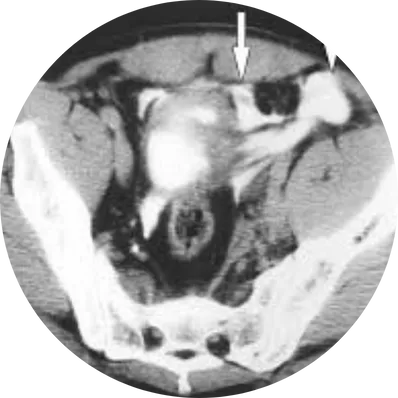

Cystectomy is a major surgical procedure to remove part (partial cystectomy) or the entire bladder (radical cystectomy). It is most often performed for muscle-invasive bladder cancer or high-risk recurrent bladder tumors. In men, it may include removal of the prostate and seminal vesicles; in women, the uterus, ovaries, and part of the vagina may also be removed. A new way for urine storage and drainage (urinary diversion) is created after surgery.

Diagnosis (Before Surgery)

Recommended for muscle-invasive or high-grade bladder cancer.